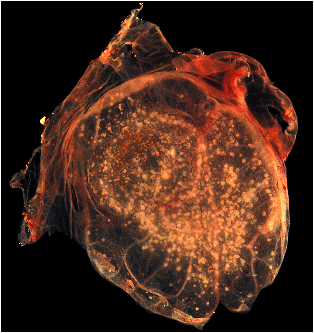

A photograph revealing smallpox virus pocks on the chorioallantoic membrane of a developing embryonic chick. Poxviruses are very easy to isolate, and will grow in a variety of cell cultures, producing characteristic hemorrhagic pocks on the chick chorioallantoic membrane (CAM). |

http://phil.cdc.gov/phil/details.asp (ID# 2542) |

1967 |

CDC/Dr. David Kirsh |